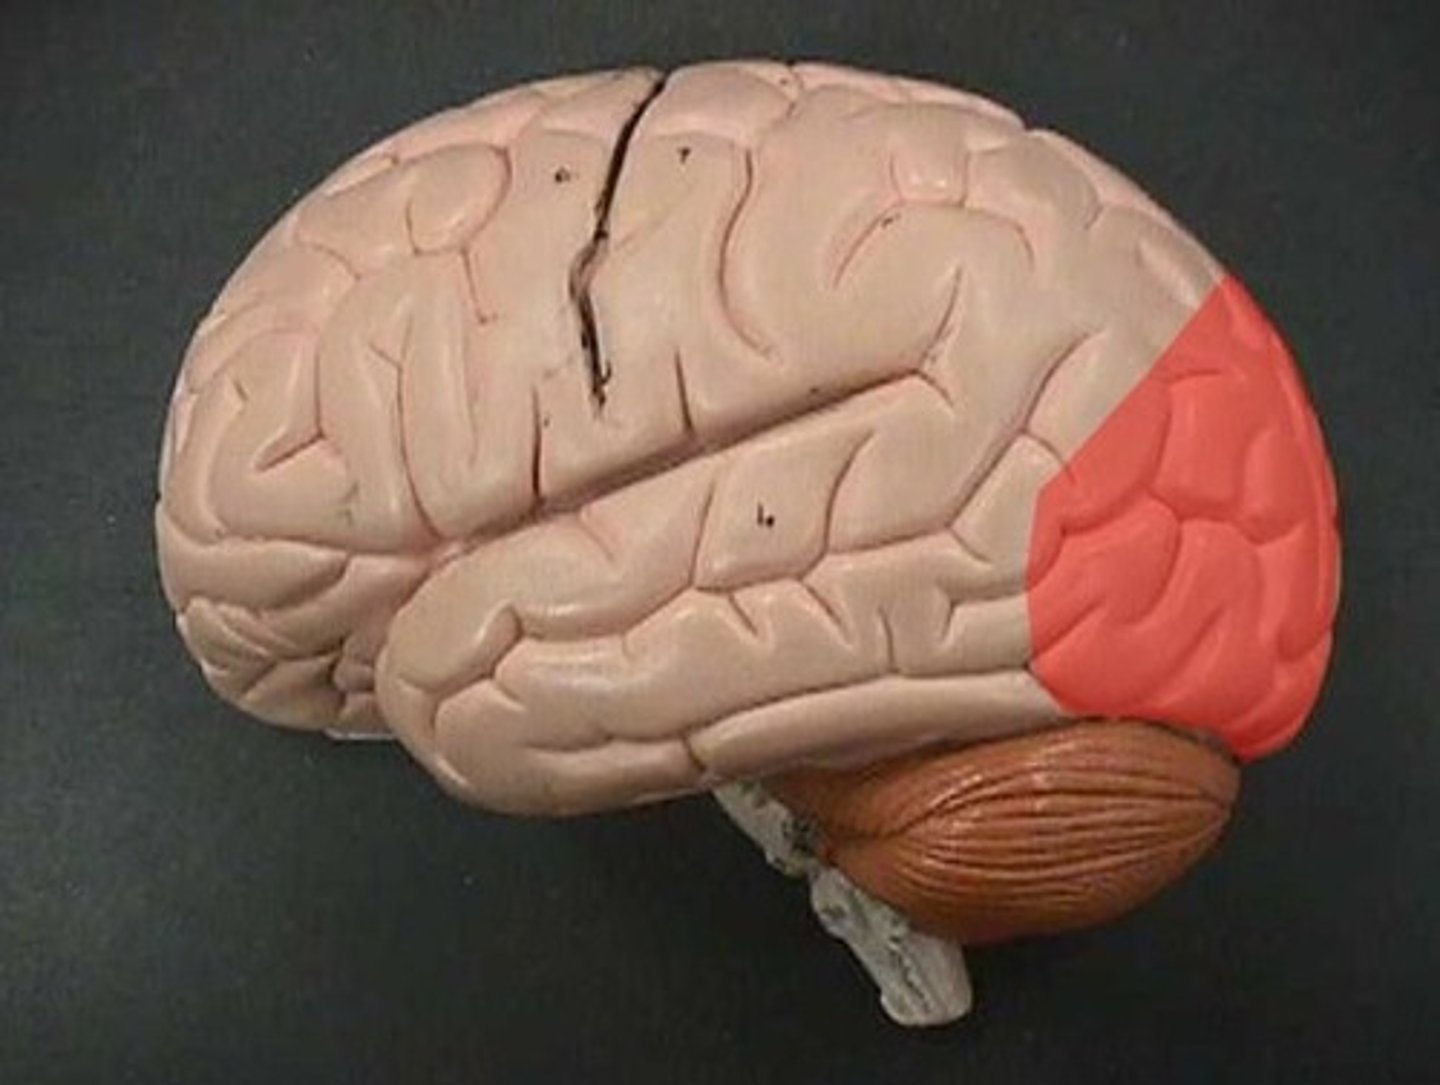

Occipital lobe

receives visual information, primarily from opposite visual field